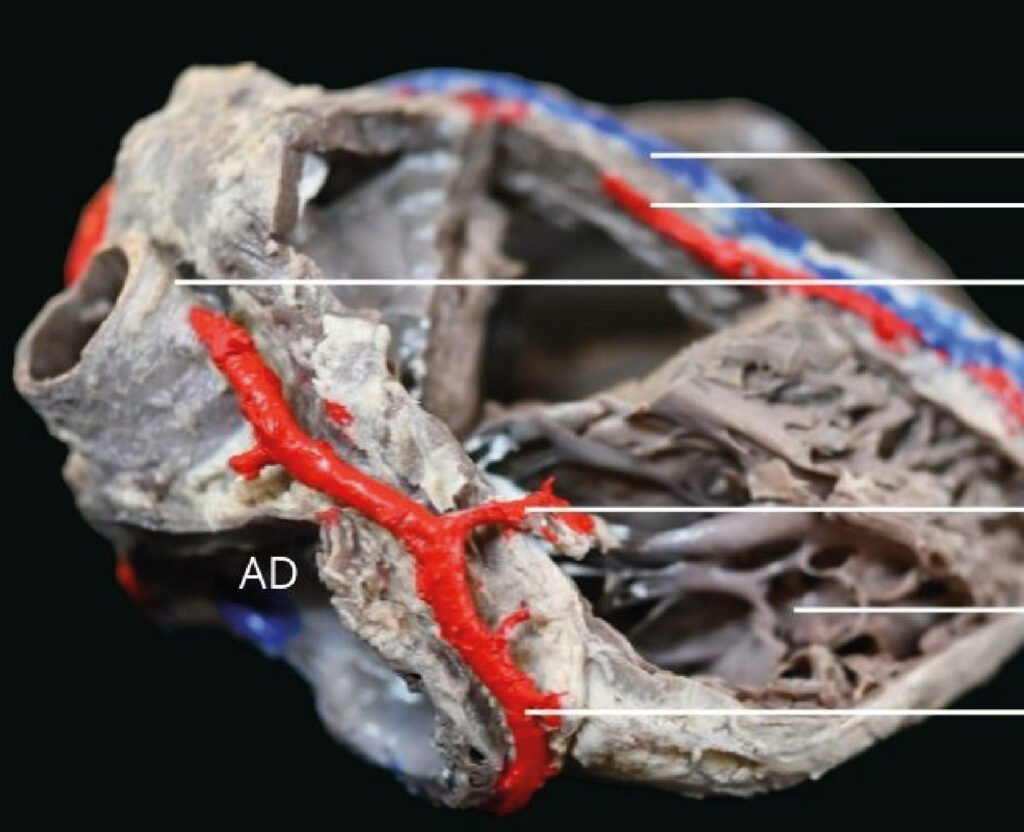

Museo.

Encontrarás los preparados de nuestro laboratorio en el museo de Anatomía J. J. Naón, Facultad de Medicina, Universidad de Buenos Aires, con su descripción.

Encontrarás los preparados de nuestro laboratorio en el museo de Anatomía J. J. Naón, Facultad de Medicina, Universidad de Buenos Aires, con su descripción.